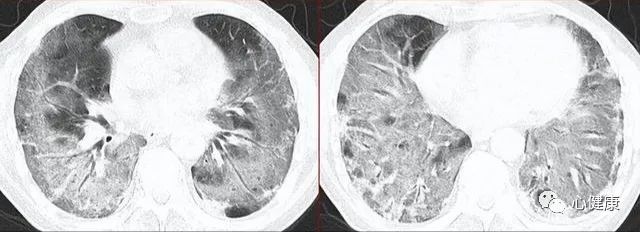

一个肺部“白”了的病人家属,说这是他们“夫妻”第一次感染新冠。上次疫情,他们很幸运的没有感染。谈话中,就感觉家属说话有尾音,追问是不是活动后胸闷?气短?家属说这两天感染后,确实有这些情况。赶紧带病人测个指脉氧——86%,肯定有问题了!再做CT,我勒个去,夫妻二人都是“白肺”无疑!

新冠病毒感染后,在一些严重病例中,新冠病毒会蔓延到肺部,导致肺部出现严重感染,肺部在射线下表现为白色,这种情况被称为“白肺”。白肺是一种肺部病变在x线下的表现,它的原因就是由于新冠病毒感染引起的。